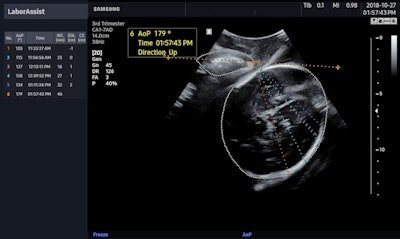

BiometryAssist provides physicians with fetal measurements in about 85 milliseconds, according to Samsung. Meanwhile, LaborAssist provides estimates of fetal AoP and head direction, which physicians can use to monitor real-time progression of delivery and determine the best delivery method, Samsung noted.

Samsung Medison's LaborAssist ultrasound image shows a fetus' angle of progression. Image courtesy of Samsung Medison.Samsung also announced that it will continue its partnership with Intel for its other artificial intelligence ultrasound solutions, including Nerve Tracking, SW Beamforming, and AI Module.